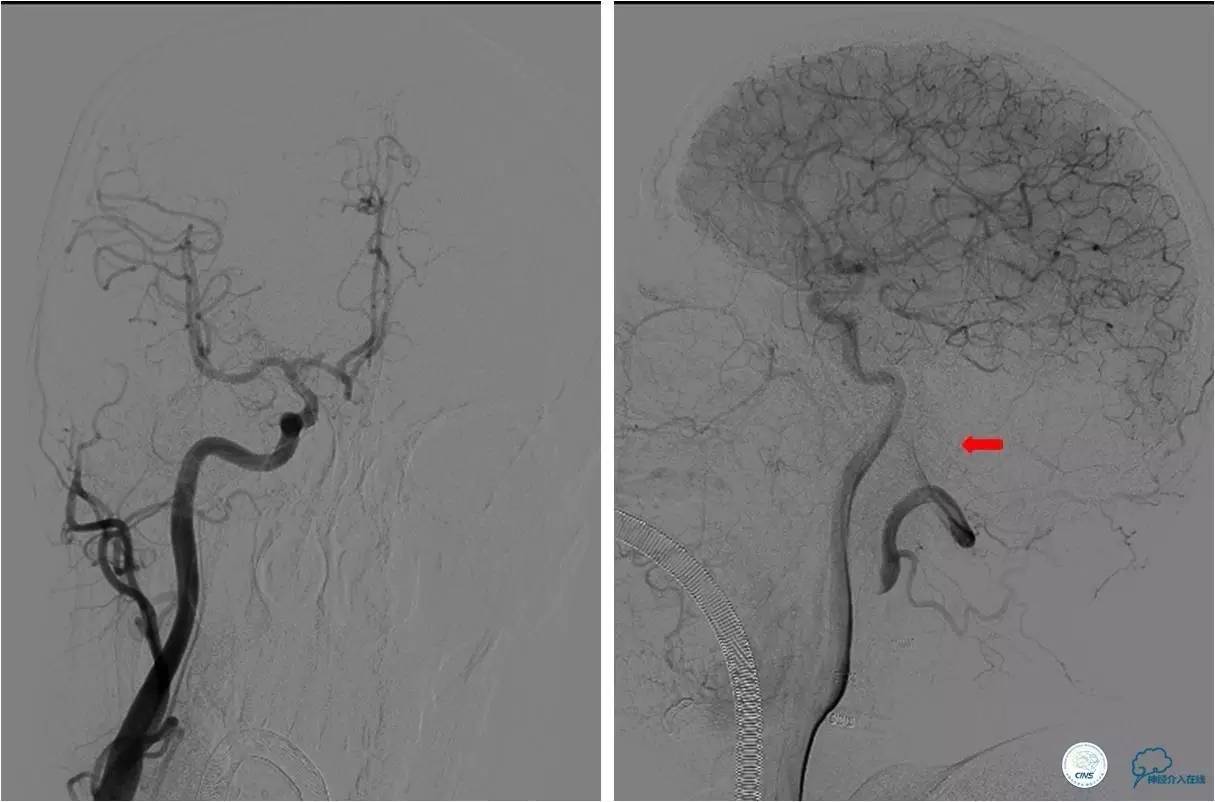

》术中造影

★右侧椎动脉起始端长段闭塞,右侧颈深动脉向右侧椎动脉供血,远端基底动脉不显影;左侧椎动脉纤细,V3段以远不显影。

★右侧颈总动脉正侧位,可见右侧枕动脉通过肌支向右侧椎动脉供血,远端基底动脉不显影。

★2.0x20 mm球囊扩张后,右椎动脉起始段见前向血流,将6F navien颅内支撑导管送至V3段造影,见V4段有血栓,基底动脉闭塞 ;

★Solitaire 6.0x20 mm取栓支架到位造影,取栓两次后基底动脉再通。

★取栓后处理椎动脉起始端的狭窄,椎动脉开口处先放置一枚球扩支架,造影见支架远端仍有狭窄,将Solitaire 6.0x20 mm贴敷在狭窄段,造影见前向血流改善(TICI分级 3级)。